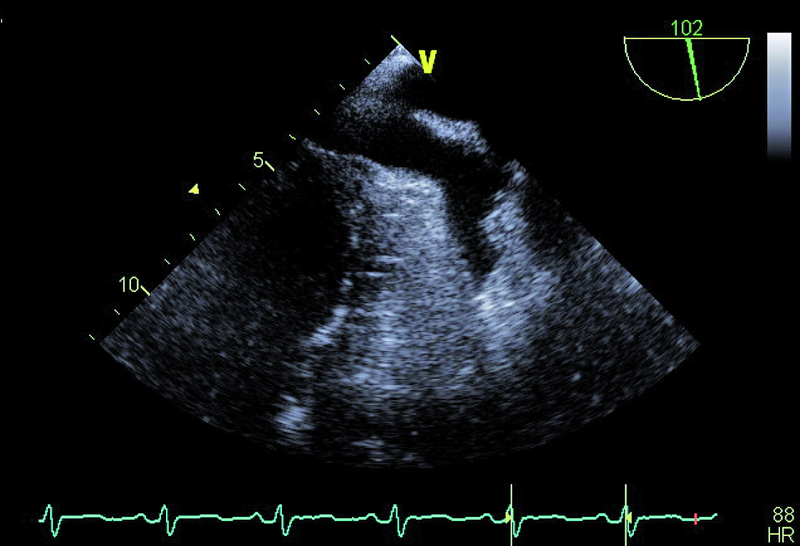

Pacjent, lat 60, z wywiadem nadciśnienia tętniczego, wieloletni palacz, został przyjęty do kliniki w celu oceny układu krążenia po przebytym rok wcześniej udarze mózgu. W przebiegu udaru obserwowano afazję ruchową, niedowład centralny nerwu VII, niedowład prawej kończyny górnej. Chory był intensywnie rehabilitowany, co przyczyniło się do stopniowego ustąpienia zaburzeń mowy oraz istotnej poprawy ruchomości prawej kończyny górnej. W tomografii komputerowej stwierdzono obszar hipodensyjny na pograniczu płata ciemieniowego i potylicznego lewej półkuli mózgu. Spektralne badanie doplerowskie tętnic szyjnych i kręgowych nie wykazało istotnych hemodynamicznie zaburzeń przepływu. Opiekujący się pacjentem neurolodzy podejrzewali, że przyczyną udaru mógł być przetrwały otwór owalny (patent foramen ovale, PFO). W wykonanych w klinice badaniach echokardiograficznych – przezklatkowym i przezprzełykowym – przegroda międzyprzedsionkowa była szczelna. Jama lewej komory była niepowiększona, a grubość mięśnia graniczna. Zwracało uwagę nieznaczne upośledzenie kurczliwości mięśnia komory (EF=50%) oraz poszerzenie aorty do 42 mm.

Wiek pacjenta, palenie tytoniu oraz chwiejne nadciśnienie tętnicze nakazują wykluczyć a priori tzw. kryptogenny udar mózgu. Przegroda międzyprzedsionkowa u chorego była szczelna, choć w badaniu przezprzełykowym (TOE) opisano śladowy kanał przetrwałego otworu owalnego (PFO), bez przechodzenia kontrastu ze strony prawej na lewą. Badanie przezprzełykowe pozwoliło także wykluczyć skrzeplinę w jamach serca (ryc. 1 – uszko lewego przedsionka) oraz istotne zmiany organiczne zastawki aortalnej (ryc. 2, 3). Prawdopodobną przyczyną udaru były nasilone zmiany miażdżycowe w łuku aorty z towarzyszącymi owrzodzeniami ściany naczynia (ryc. 4, 5). Warto zaznaczyć, że zmiany będące zgrubieniem błony wewnętrznej bywają dynamiczne i nie można wykluczyć powstawania ruchomych składowych (skrzeplin) na dużych elementach owrzodzenia. W diagnostyce miażdżycowego uszkodzenia aorty metodą z wyboru jest badanie przezprzełykowe, pozwalające zidentyfikować dzięki wysokiej rozdzielczości obrazu drobne, nawet kilkumilimetrowe owrzodzenia. Warto zaznaczyć, że badanie przezklatkowe nie dostarcza tak wyraźnego i jednoznacznego obrazu (ryc. 6). Korzyść z badania echokardiograficznego jest bez wątpienia większa niż z badania TK czy MR, ze względu na możliwość oceny ruchomości blaszek w czasie rzeczywistym. W rutynowej ocenie zwraca się uwagę na grubość blaszki miażdżycowej, obecność owrzodzeń, zwapnień oraz nałożonych ruchomych ech odpowiadających skrzeplinom – stanowiących tzw. potencjał zatorowy blaszki. Uważa się, że średnica blaszki przekraczająca 4 mm ma większy potencjał zatorowy niż owrzodzenie płytkie (w przedstawionym przypadku średnica blaszki wynosiła 7 mm). Dowiedziono ponadto, że w przypadku blaszek nieuwapnionych – jak w opisanej sytuacji – ryzyko zatoru jest większe niż w przypadku blaszek uwapnionych. Leczenie antykoagulacyjne w takim wypadku jest uzasadnione. Konieczne jest także włączenie dużej dawki statyn mimo braku zmian miażdżycowych w tętnicach wieńcowych (wykonano koronarografię). Ocena układu krążenia u pacjenta po przebytym incydencie zatorowym do OUN powinna być kompleksowa i powinna uwzględniać wszystkie możliwe nieprawidłowości.